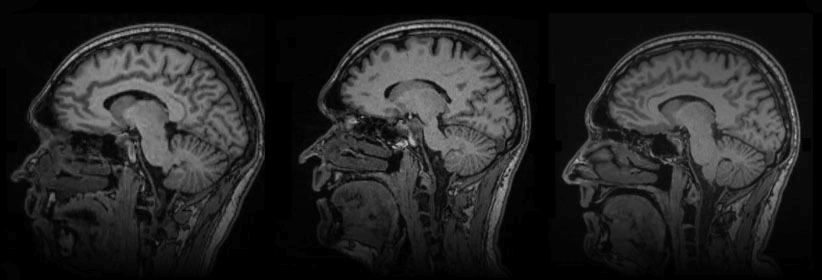

Magnetic Resonance Imaging (MRI)

High-field open MRI using the Hitachi Altaire — clinically rigorous, with a fully open design that eliminates the enclosed tunnel experience.

Dr. Christel Bauer, MD

Diagnostic Radiologist. Graduate of Cornell University Medical College, 1988. Over 29 years of experience with subspecialty focus in Neuroradiology. Specialty: Diagnostic Radiology · Subspecialty: Neuroradiology